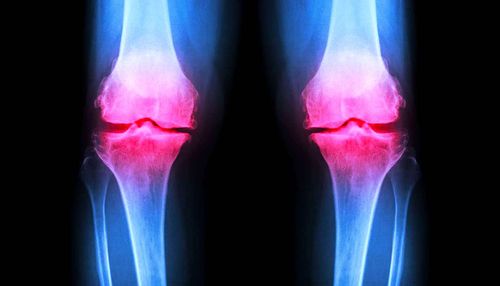

Suite à un accident, à une maladie ou au vieillissement naturel des articulations, le cartilage peut devenir irrémédiablement endommagé, engendrant douleurs et problèmes de mobilité. Un nouvel hydrogel pourrait considérablement améliorer le traitement des lésions cartilagineuses. Les propriétés uniques de ce gel, qui fournit un échafaudage sur lequel les cellules